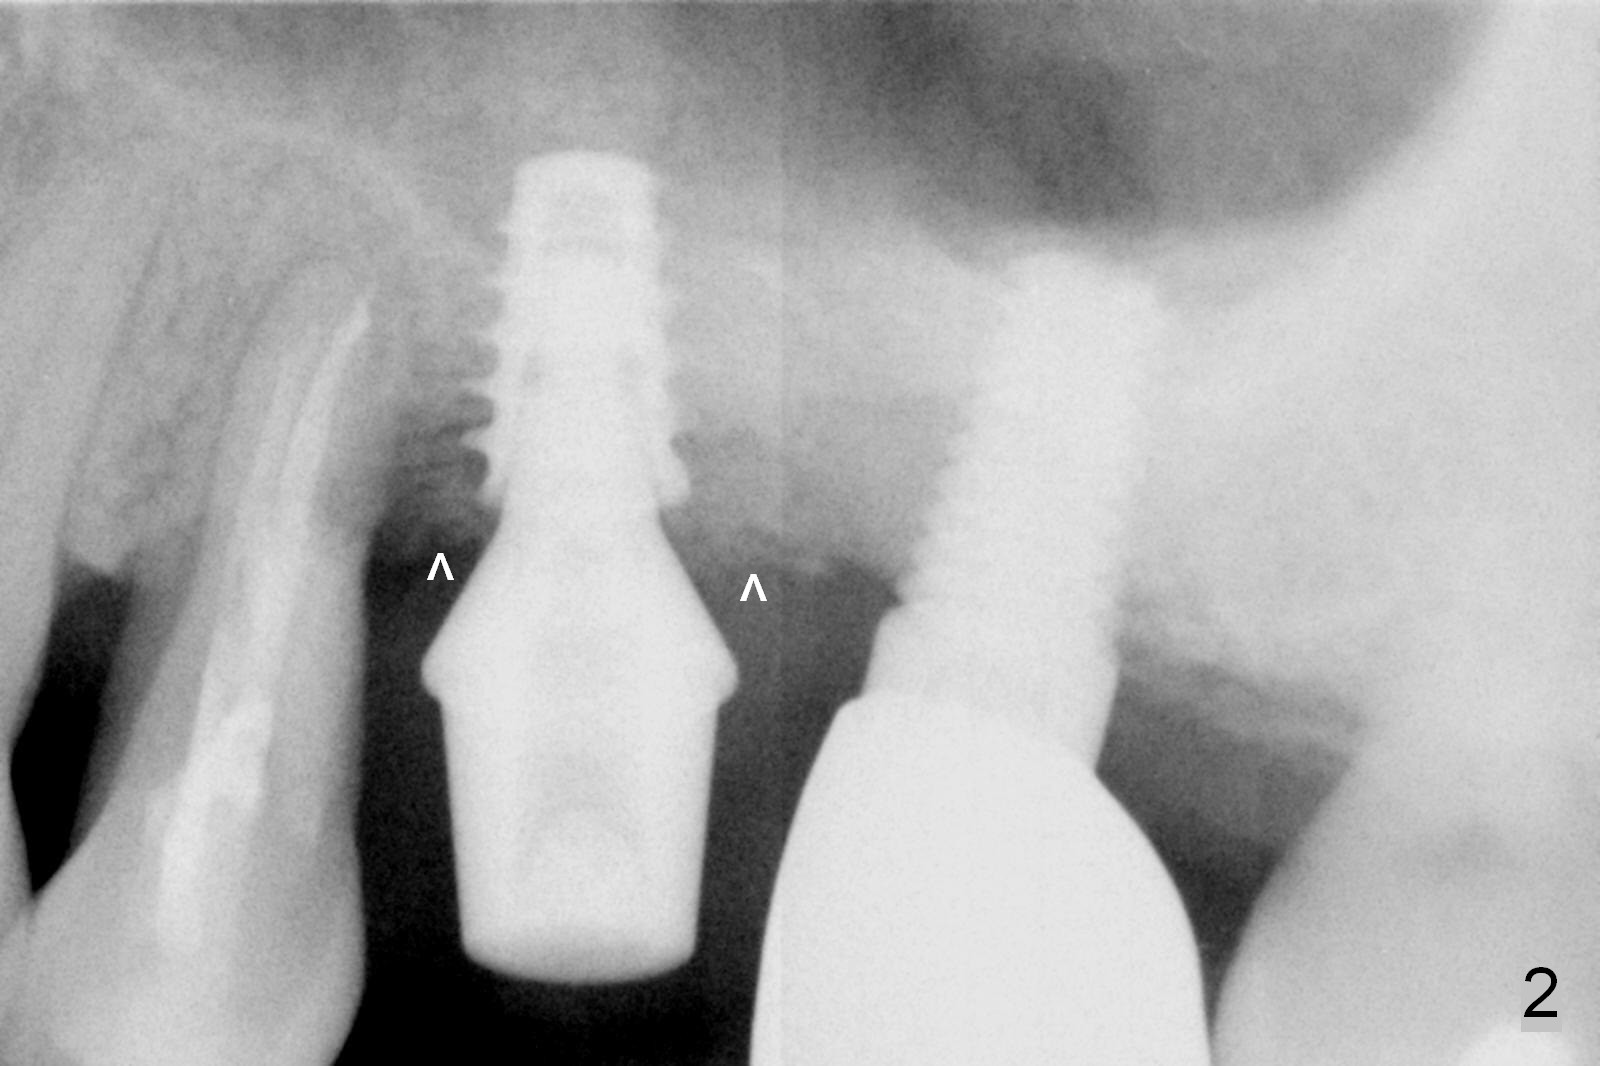

Four months post bone graft, the bone height at #14 is ~ 5 mm (Fig.1). After osteotomy for 4 mm with 4.3 mm Magic Drill (hard bone), Magic Sinus Lifter is used for sinus lift for ~ 8 mm without sinus membrane perforation. Perforation occurs with pulsating hemorrhage after sinus lift with allograft (.5-1 mm, mixed with Metronidazole). Collagen plug is used to repair the perforation before placing a short (5x7 mm) IBS implant with ~ 25 Ncm (Fig.2). After placing a 6.5x5.7(3) mm abutment, allograft is placed around the most coronal exposed implant thread (^). Acrylic is applied over the abutment for wound protection. There is mild nasal hemorrhage for 2 days postop. To prevent and treat sinus membrane perforation, PRF will be routine prepared preop for future cases. New bone forms apically and coronally 4.5 months postop (Fig.3,4 ^). A new temporary crown is fabricated so that it can undergo progressive loading for a few months before final impression. The definitive restoration is delivered 7.5 months postop (Fig.5). The bone density apical to the implant becomes apparently denser nearly 5 months post cementation (Fig.6). The bone density in the crest increases 2 years post cementation (Fig.7 *).